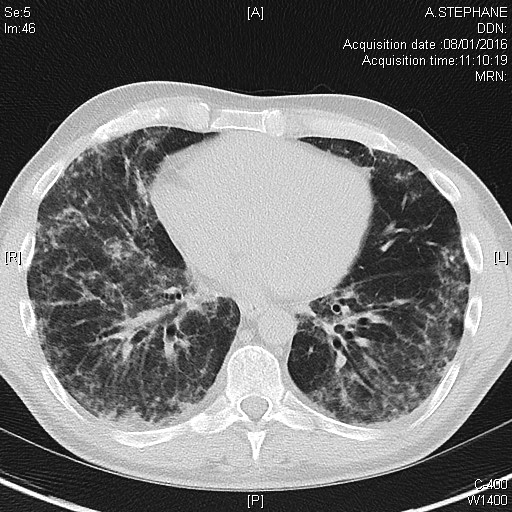

Pneumopathie interstitielle dans le cadre d'une myopathie inflammatoire à anticorps anti-MDA5